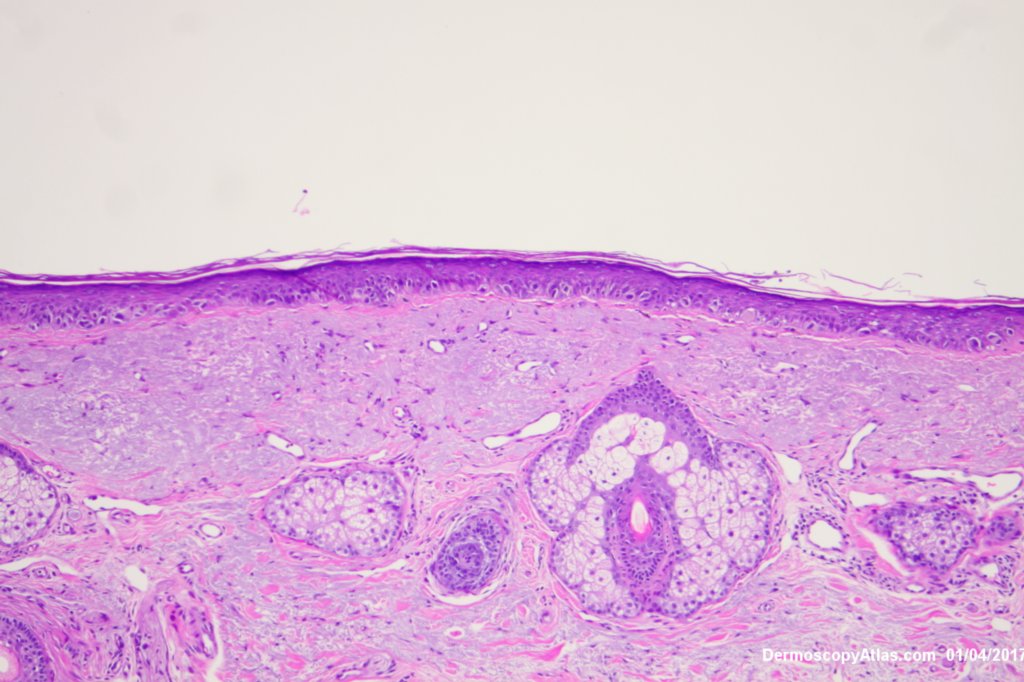

Description: Lentiginous proliferation of atypical melanocytes

The Dermatoscopy shows partial grey circles and the histology shows a lentiginous proliferation of atypical melanocytes involving the hair follicles.